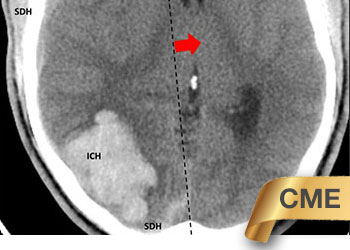

Endovascular:

CME:

Symptomatic Near-Occlusion of the Carotid Artery

Author: Jonathan L. Brisman M.D., F.A.C.S., Read More!